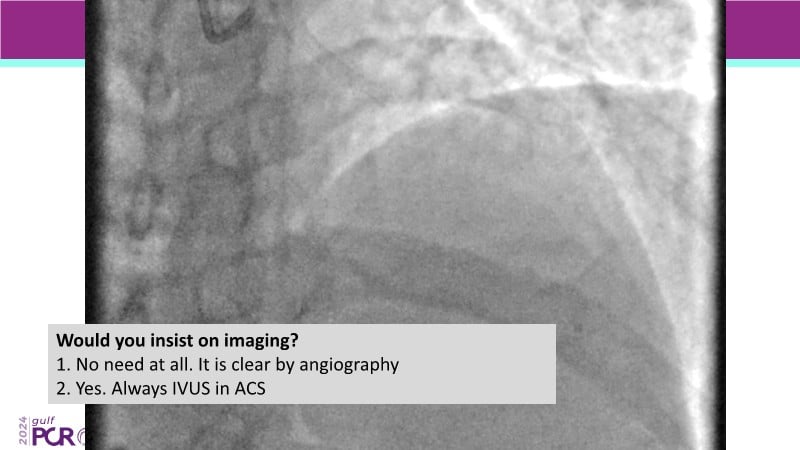

Explore cutting-edge strategies for optimizing drug-coated balloon (DCB) procedures in this session. Uncover practical tips to improve outcomes, review key indications, and examine international consensus on DCB use. Case presentations and expert discussions offer insights to refine your approach.